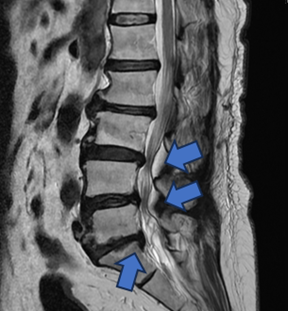

手術以間接減壓的方式,從後腹腔進入(紅色箭頭),有別傳統從脊椎腔(藍色箭頭)切入,因此能夠不破壞骨骼不撥弄脊椎神經,大幅減低神經損傷機率。

手術以間接減壓的方式,從後腹腔進入(紅色箭頭),有別傳統從脊椎腔(藍色箭頭)切入,因此能夠不破壞骨骼不撥弄脊椎神經,大幅減低神經損傷機率。官方提供